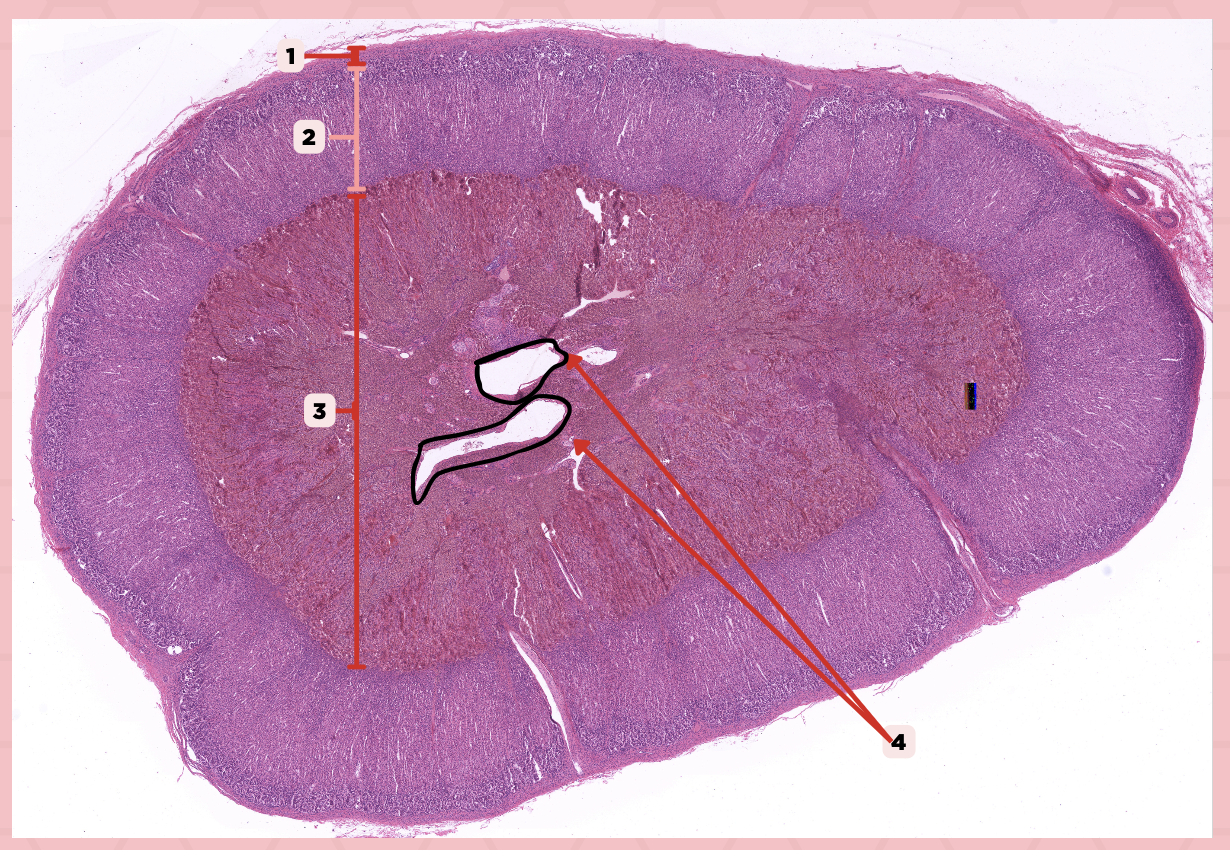

Identify the specimen.

Anterior Lobe

Identify the structure labeled as 1.

Posterior Lobe

Identify the structure labeled as 2.

Intermediate Lobe

Identify the structure labeled as 3.

Pars Tuberalis

Identify the structure labeled as 4.

Pituitary Stalk

Identify the structure labeled as 5.